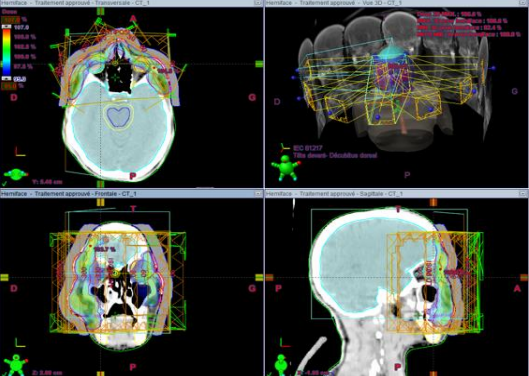

The patient was given a skin biopsy of the different lesions with an anatomopathological and immunohistochemically study in favor of a folicullotropic type fungal mycosis with cervical thoracic abdomino pelvic scan performed as part of the extension assessment: presence of the adeno-pathological, bilateral cervical axillary classifying the tumor: a stage IIB according to the classification EORTC; then she received systemic treatment with methotrexate and corticosteroid infiltrations for facial lesions, and given the increase in size of the face and back, a Gemcitabine-based mono-chemotherapy was administered, However, as the patient had an allergic reaction similar to a drug-like hepatitis following the introduction of two courses of Gemcitabine, the decision to have external radiotherapy was made. The latter was made by three-dimensional conformational technique: at a dose of 30 Gy in 10 fractions on the lesions of the face and on the lesions of the back with good tolerance and almost complete regression of the lesions described above. (Fig2)

Fig. 3: Dosimetry image of our patient showing the coverage of different volumes.